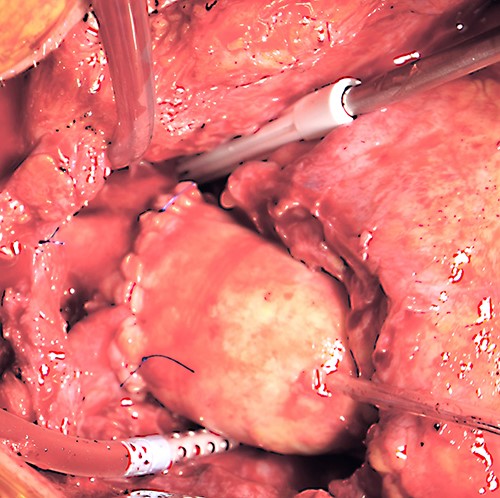

After cardiopulmonary bypass initialization and opening the sternum, one could see the fistula path affecting only the left side of the manubrium sterni and reaching into the mediastinum. Around the ascending aorta was an infected hematoma, with clear infiltration of the Dacron patch, no signs of aortic root abscess or infection. The patient underwent hypothermic circulatory arrest with selective antegrade brain perfusion. The ascending aorta and the proximal two-thirds of the aortic arch were replaced with a cryopreserved aortic homograft (Fig. 2). The fistula path together with the manubrium sterni and the cartilage to the second left rib were completely resected. The rib was then fixated to the right side of the sternum using a titanium plate. The remaining sternum was treated with antiseptic solution and was then conventionally closed with sternal wires. The pectoralis major was mobilized on both sides together with the skin and was used to stabilize the wound.

Intraoperative photograph demonstrating the surgical result after homograft replacement of the ascending aorta and aortic hemiarch.